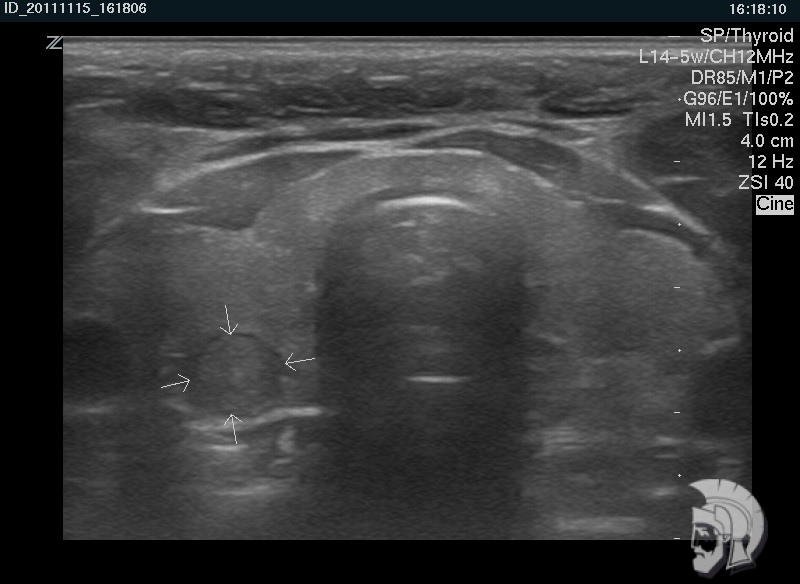

| Фото правостороннего узлового зоба у мужчины 28 лет. Узел в задних отделах правой доли указан стрелками |

| Фото правостороннего узлового зоба. Тот же случай |